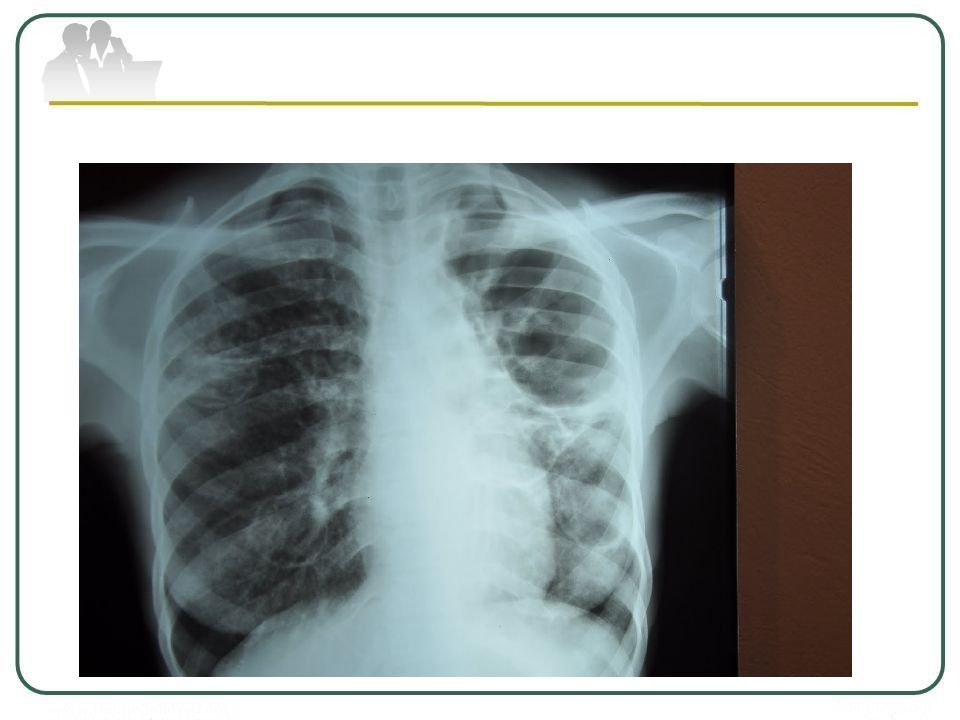

Иллюстрации по теме очагового и инфильтративного туберкулеза

Раздел: Фотодневник открытий